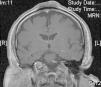

The patient was a 62 year-old man with no relevant past medical history other than the practice of an inverted yoga posture for 30minutes several times a day since the age of 15. He presented with a persistent, asymptomatic, raised lesion in the interparietal region that had appeared more than 20 years previously. The size of the lesion had increased during the first few years and then subsequently stabilized. Occasional ulceration and infection of the lesion resolved spontaneously or after antibiotic treatment for approximately 10 days. Physical examination revealed a hard, oval-shaped, tuberous lesion in the interparietal region of about 10cm in anteroposterior length and 6cm in width with a centrally eroded surface (Fig. 1,A and B). Blood tests revealed no significant abnormalities. Radiograph of the skull showed an increase in soft tissue in the parietal region and associated periosteal reaction. Based on these findings, a contrast-enhanced computed tomography scan of the brain was performed, revealing an extracranial soft-tissue mass in the upper frontal convexity along the midline, with discrete underlying periosteal reaction and no clear involvement of the outer table of the diploe, consistent with a reactive process. Skin biopsy showed marked orthokeratotic hyperkeratosis and mild epidermal acanthosis. The dermis showed focal fibrosis with proliferation of small vessels, dense perivascular lymphocytic infiltrates, and isolated siderophages (Fig. 2,A and B). Magnetic resonance imaging of the brain revealed thickening of extracranial soft tissue at the level of the coronal and sagittal sutures and the external table. The latter showed hypointensity in all sequences indicating sclerotic bone reaction. These findings were consistent with fibrotic changes affecting the extracranial soft tissues and sclerotic bone reaction in the underlying cortical bone (Fig. 3).